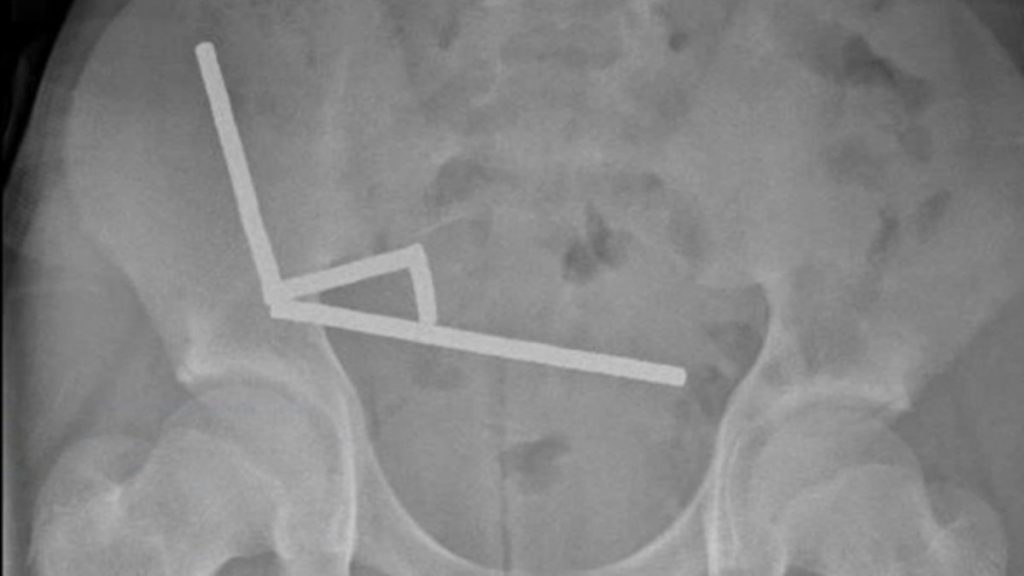

Életmentő műtéten esett át egy új-zélandi tinédzser, aki veszélyes online kihívást teljesített. A tizenéves közel 200 mágnest nyelt le, azok azonban összekapcsolódtak a beleiben, és szövetelhalást okoztak.

Életveszélybe került egy 13 éves új-zélandi fiú, miután közel 200 mágnest lenyelt, ezzel súlyos sérülést okozva a bélrendszerében – írja a Science Alert.

A tinédzser hasi panaszokkal ment a Tauranga Kórházba, ahol az orvosoknak elmondta, hogy egy héttel korábban körülbelül 100 darab mágnest nyelt le. Az orvosok az azonnali műtét mellett döntöttek, a feltárás során azonban kiderült, hogy a tizenéves közel 200 mágnest nyelt le.

A mágnesek egymáshoz tapadva összesen 4 láncot alkottak, amiket az orvosok a fiú bélrendszerének különböző szakaszaiból emeltek ki. A mágnesek több szövetben is nekrózist okoztak, a szövetelhalás miatt az orvosok a bélrendszer egy részét eltávolították.